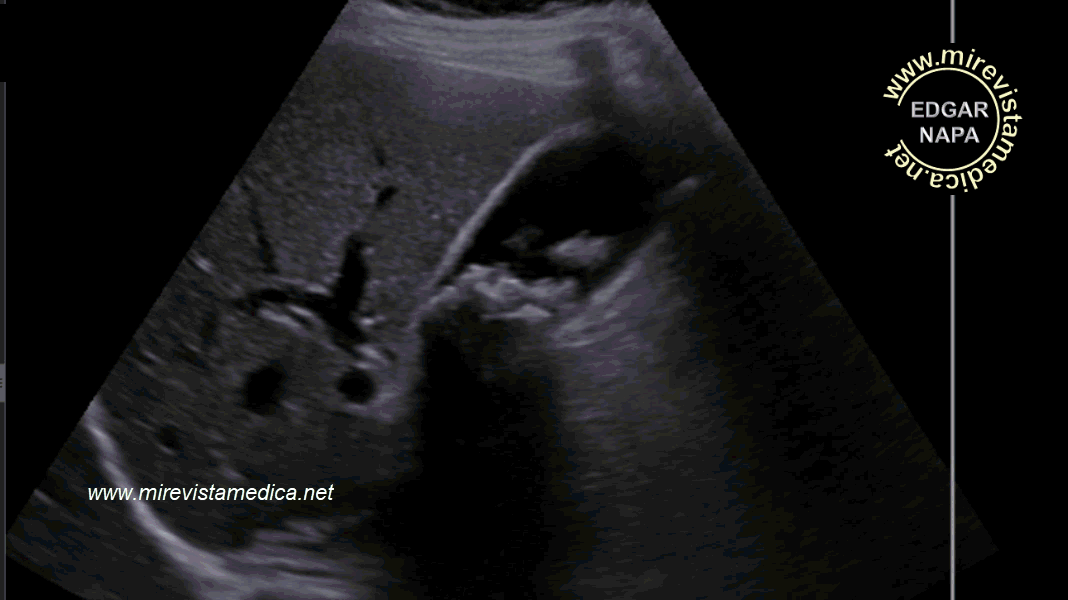

Semiología de los conductos intra y extrahepáticos en ultrasonido